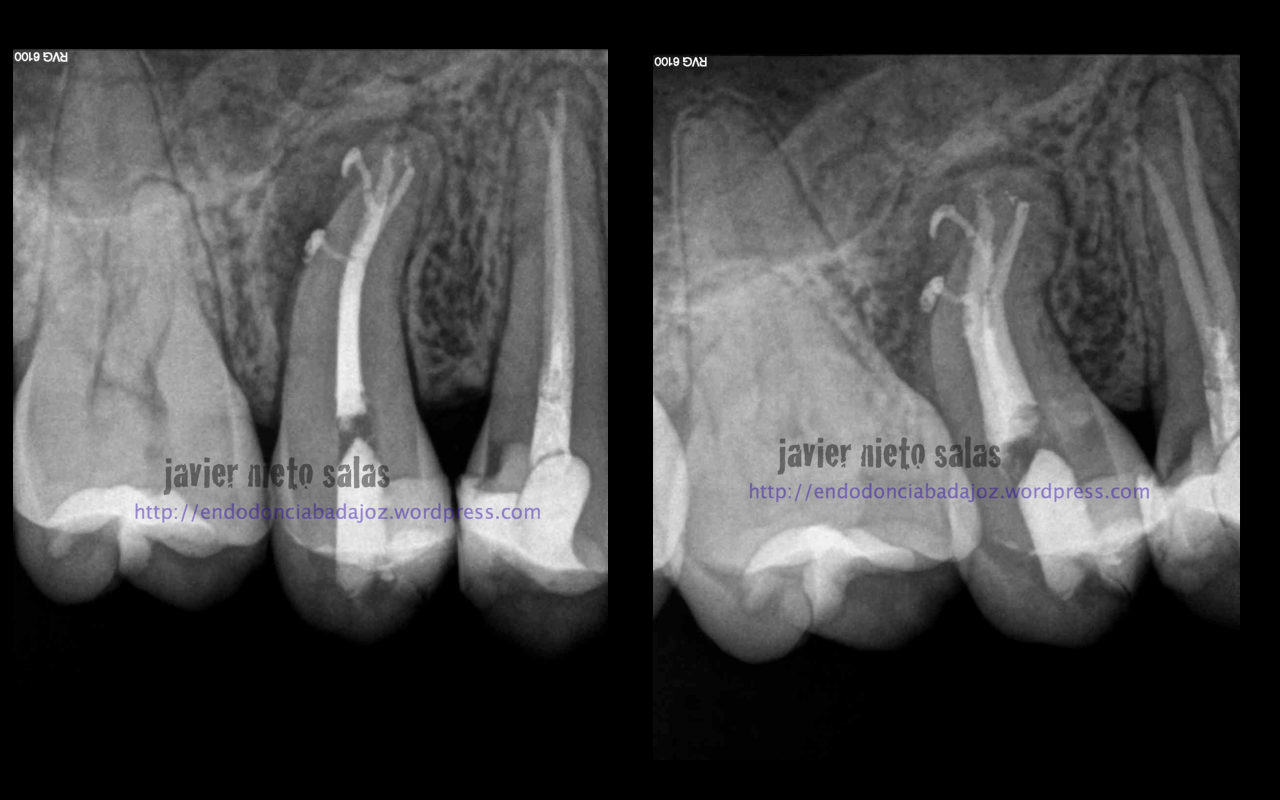

Hay casos más o menos complicados, que debemos plantearnos como afrontarlos, y en ocasiones nos sorprenden con esos conductos laterales que obturamos por la buena limpieza y obturación que empleamos.

O por el contraio este otro, que he de decir que me costó muchísimo, pero que gracias a poder estudiar el caso y a la ayuda de la magnificiación pudimos tratarlo correctamente: